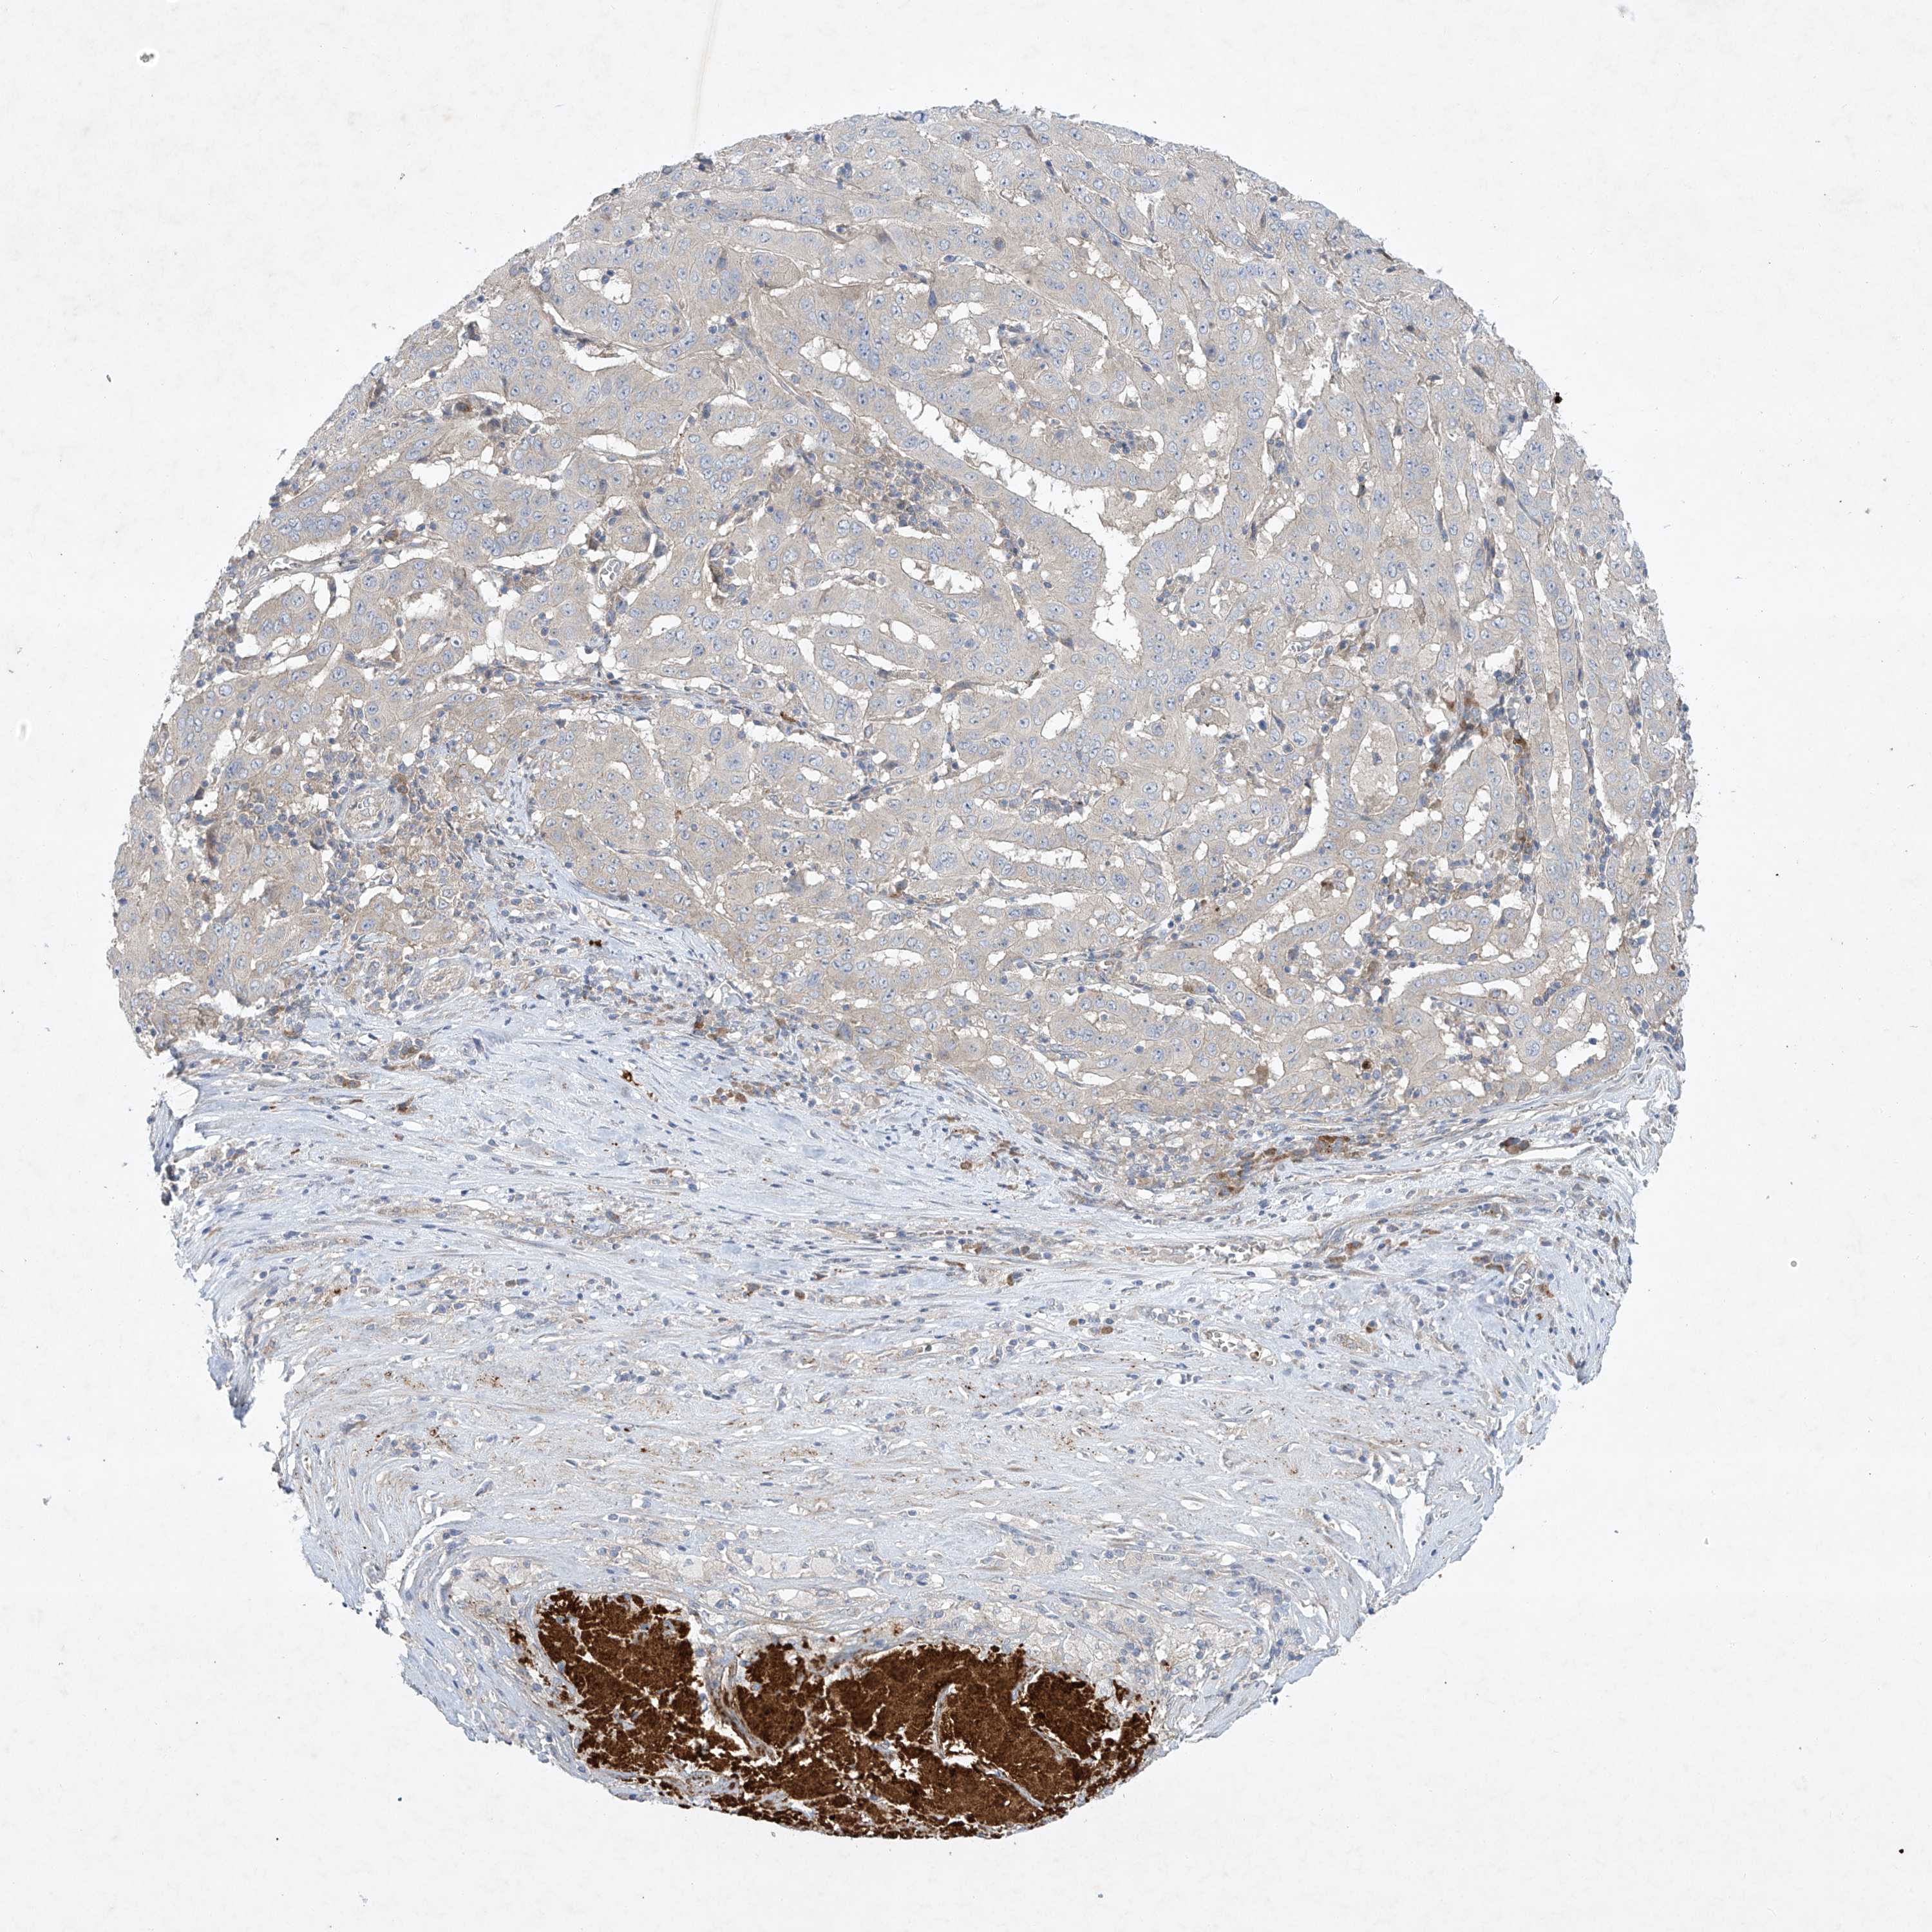

PANCREATIC CANCER - Protein expressioni

A mouse-over function shows sample information and annotation data. Click on an image to view it in a full screen mode. Samples can be filtered based on level of antibody staining by selecting one or several of the following categories: high, medium, low and not detected. The assay and annotation is described here.

Note that samples used for immunohistochemistry by the Human Protein Atlas do not correspond to samples in the TCGA dataset.

Antibody stainingi

Antibody staining in the annotated cell types in the current human tissue is reported as not detected, low, medium, or high, based on conventional immunohistochemistry profiling in selected tissues. This score is based on the combination of the staining intensity and fraction of stained cells.

Each image is clickable and will lead to virtual microscopy that enables deeper exploration of all samples and also displays staining intensity scores, fraction scores and subcellular localization as well as patient and tissue information for each sample.

Antibody HPA030164

Antibody HPA030165

Antibody HPA030166

Adenocarcinoma, NOS